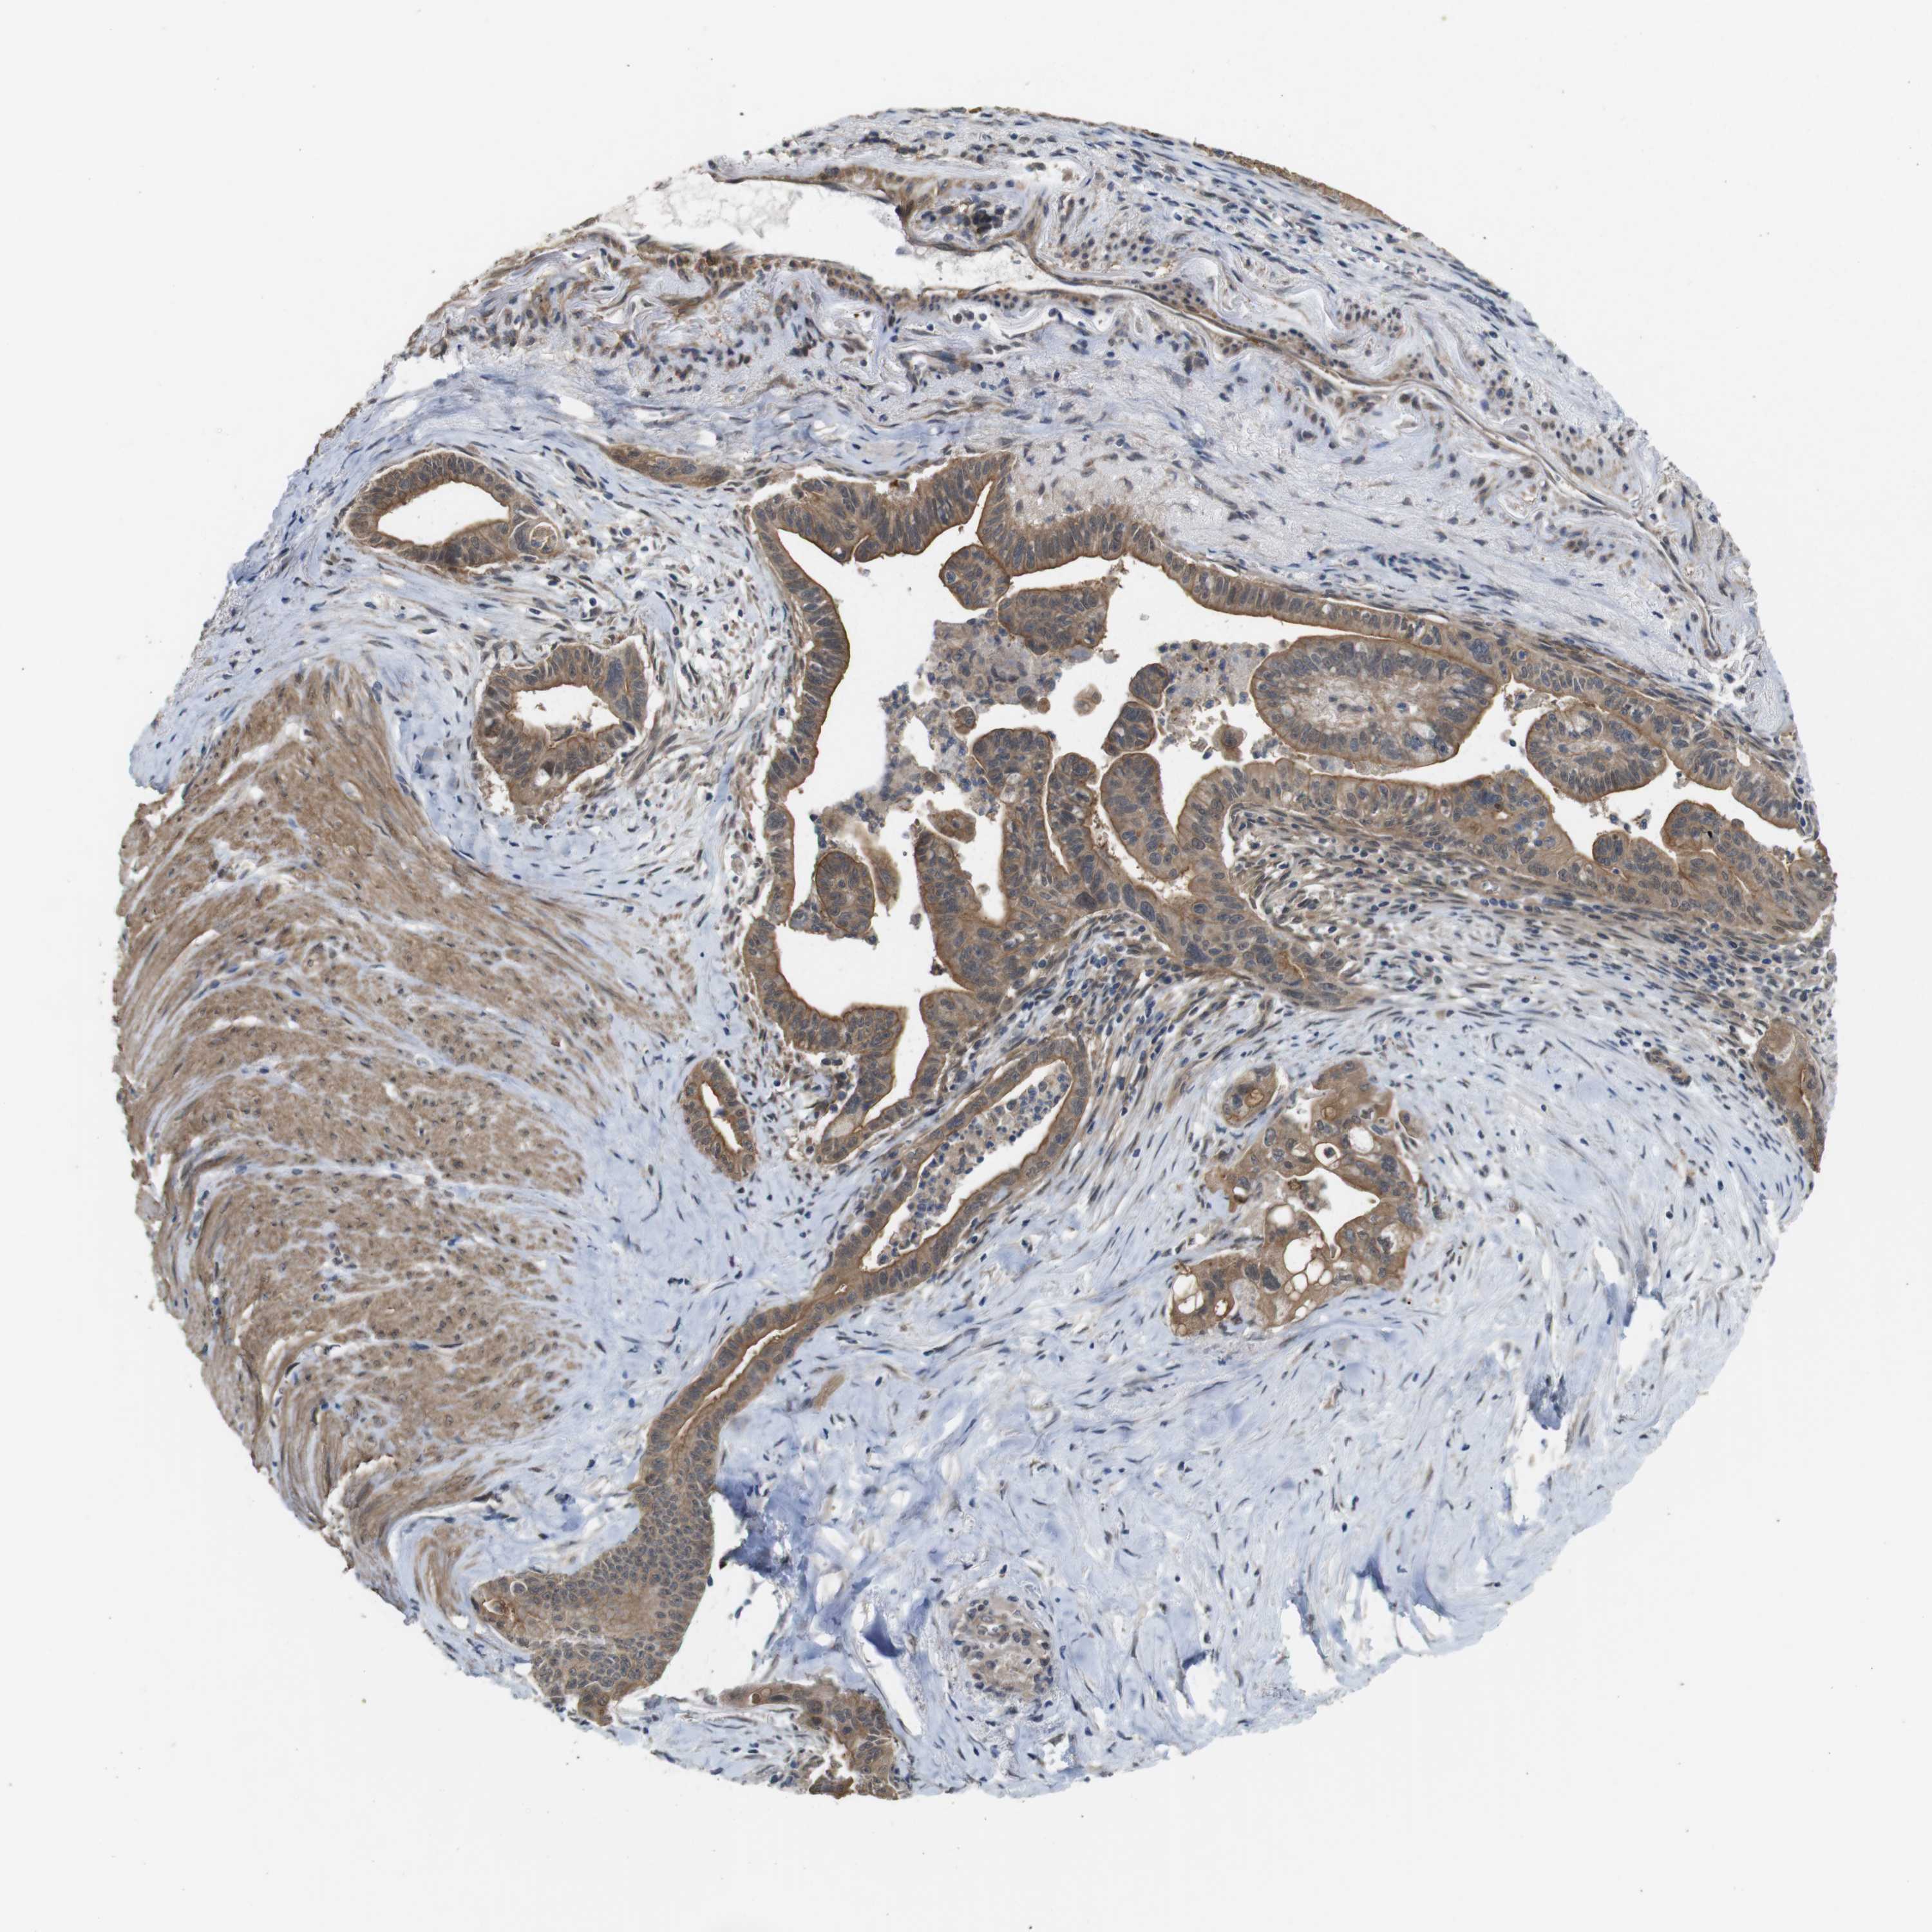

PANCREATIC CANCER - Protein expressioni

A mouse-over function shows sample information and annotation data. Click on an image to view it in a full screen mode. Samples can be filtered based on level of antibody staining by selecting one or several of the following categories: high, medium, low and not detected. The assay and annotation is described here.

Note that samples used for immunohistochemistry by the Human Protein Atlas do not correspond to samples in the TCGA dataset.

Antibody stainingi

Antibody staining in the annotated cell types in the current human tissue is reported as not detected, low, medium, or high, based on conventional immunohistochemistry profiling in selected tissues. This score is based on the combination of the staining intensity and fraction of stained cells.

Each image is clickable and will lead to virtual microscopy that enables deeper exploration of all samples and also displays staining intensity scores, fraction scores and subcellular localization as well as patient and tissue information for each sample.

Antibody HPA002382

Antibody CAB005109

Antibody CAB047311

Staining

High

Medium

Low

Not detected

Intensity

Strong

Moderate

Weak

Negative

Quantity

>75%

75%-25%

<25%

None

Location

Nuclear

Cytoplasmic/membranous

Cytoplasmic/membranous,nuclear

Adenocarcinoma, NOS

Adenocarcinoma, metastatic, NOS